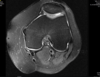

Superficial fissuring of the lateral patellar facet cartilage, normal patellar ratios, TTTG 26mm

Isolated 2cm2 grade 4 chondral defect of the lateral patella facet with a normal trochlea.